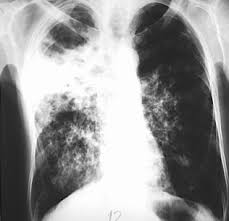

Tuberkulosis (TBC)

• Penyebab: Penyakit TBC disebabkan oleh basil Mycobacterium tuberculosis. Penyakit ini sanggup menular melalui percikan ludah ketika penderita batuk.

• Gejala: Batuk berdahak lebih dari tiga minggu. Dapat juga disertai batuk yang mengeluarkan darah. Penderita akan mengalami demam khususnya pada siang atau sore, berkeringat pada malam hari. Nafsu makan menurun sehingga menimbulkan tubuh menjadi kurus.

• Pencegahan dan solusi: Bila ada teman, tetangga atau anggota keluarga yang mengalami tanda-tanda tersebut, ada baiknya Anda menyarankan untuk memeriksakan ke dokter untuk mengetahui apakah batuknya merupakan penyakit TBC atau tidak. Karena kadangkala penyakit batuk sering dianggap sepele, padahal penyakit ini sanggup membunuh seseorang jikalau tidak segera ditangani dan sanggup menular kepada orang lain.

• Pengobatan: Pengobatan untuk TBC jikalau sudah diketahui semenjak dini bahu-membahu tidak terlalu mahal dan gampang untuk disembuhkan lantaran sudah ada obat yang disediakan pemerintah. Bila diperlukan, penderita TBC sanggup juga dikarantina di tempat khusus supaya tidak menularkan penyakitnya.

Penyakit ini juga bahu-membahu merupakan salah satu penyakit yang sudah ditaklukan, tetapi belakangan kembali menyerang. Salah satunya yaitu lantaran penderita tuberkulosis ini tidak menghabiskan obat mereka. Obat harus diminum secara teratur selama 6 hingga 9 bulan untuk menyembuhkan penyakit ini. Tidak menghabiskan obat sanggup menimbulkan penderita tidak sanggup sembuh dan menimbulkan obat tidak bisa lagi melawan kuman lantaran kuman menjadi kebal.